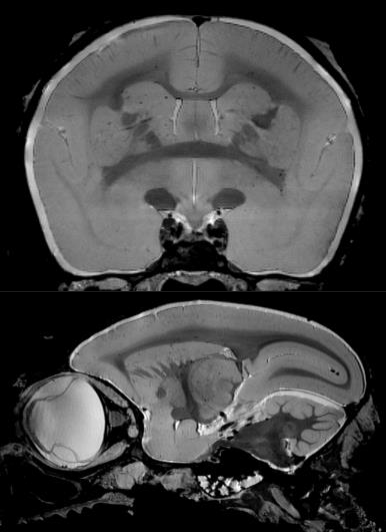

1、高分辨率神经解剖结构

布鲁克结合超高磁场,先进的相阵控线圈和谱仪技术提供完美品质的结构形态成像。超高空间分辨率可以显示精细的显微组织结构。领先的磁共振成像技术在超高磁场下提供完美的对比度。

磁共振成像低温探头增加150%的灵敏度,清晰显示小鼠脑部细胞层状结构(小脑的颗粒层和浦肯雅细胞层),空间分辨率达到 50µm: